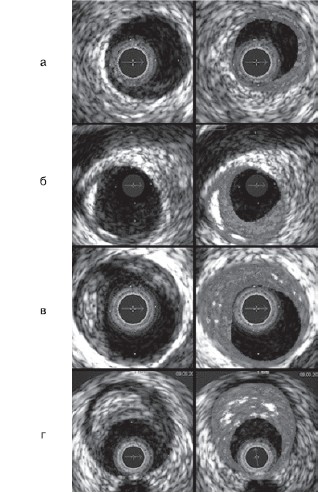

После проведения автоматического спектрального анализа данных ВСУЗИ изображение АБ разделялось на 4 основных компонента, которым присваивалась соответствующая цветовая кодировка: фиброзный — зеленый, фиброзно-липидный — зелено-желтый, участки некроза — красный, зоны кальциноза — белый цвет. Согласно принятой классификации [5], АБ разделялись на 4 основные типа (рис. 1):

- •патологическое утолщение интимы — в основном содержит фиброзный и фиброзно-липидные компоненты с зоной некроза и участками кальциноза ≤3% площади АБ (см. рис. 1, а);

- •фиброкальцинированная атерома — состоит преимущественно из фиброзной ткани с участками кальциноза и некроза, занимающими 3—10% площади бляшки (см. рис. 1, б);

- •фиброатерома — АБ с содержанием некротического ядра более 10%, которое покрыто визуализируемой фиброзной капсулой (см. рис. 1, в);

- •фиброатерома с тонкой капсулой — АБ, занимающая более 40% площади просвета артерии с содержанием некротического ядра более 10% объема АБ, непосредственно прилегающего к просвету артерии (должна визуализироваться в 3 последовательных поперечных изображениях; см. рис. 1, г).

Рисунок 1. Классификация атером на основе данных ВСУЗИ-РД (Nair A 2002).

а — патологическое утолщение интимы; б — фиброкальцинированная АБ; в — фиброатерома; г — ФАТК. АБ — атеросклеротическая бляшка; ФАТК — фиброатерома с тонкой капсулой; РД — радиочастотные данные; здесь и на рис. 2: ВСУЗИ — внутрисосудистое ультразвуковое исследование.